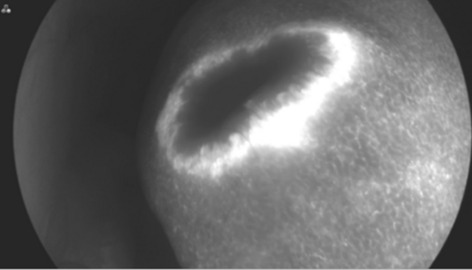

Result: The comparative analysis of the data shows a decrease in the number of presentations in ESU of AC cases during the pandemic, compared to the previous year, most often due to patients' fear of contacting the virus in the hospital environment. The median time between the onset of symptoms and the presentation in the ESU: 2020 – 14 days, 2019 – 5 days. Forms of moderate and severe AC predominated in the pandemic: GradeI—14.28%; GradeII—57.14%; GradeIII—28.57%. In 2019 GradeI—66.39%, GradeII—27.73%, GradeIII—5.88%. Laparoscopic cholecystectomy was attempted for all patients from the beginning, but the complications identified during surgery and severe forms led to a conversion rate in 2020 of 14.28%, compared to 5.88% in 2019. The severity of the cases is also observed in the postoperative complications encountered (perihepatic abscess Fig. 2. Figure 2, wound infection, bile leak; 2019—5.04%, 2020—23.21%), which required surgical reinterventions to solve them (2019: 2.52%, 2020: 10.71%). The number of deaths was significantly higher in 2020 (5.35%), compared to 2019 (0.84%).

Conclusion: Neglecting this pathology frequently encountered in ESU can lead to life-threatening complications and therefore we argue that a laparoscopically resolved cholecystectomy even in the "Covid19 era" remains the gold standard, guaranteeing the best results. Initially attempted conservative treatment may be a solution, but in the long term it can lead to severe complications and high costs.